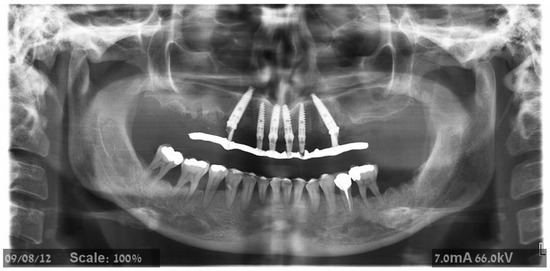

2.2. Surgical Treatment

2.4.4. Radiographic Measurements

3.1. Demographic Data